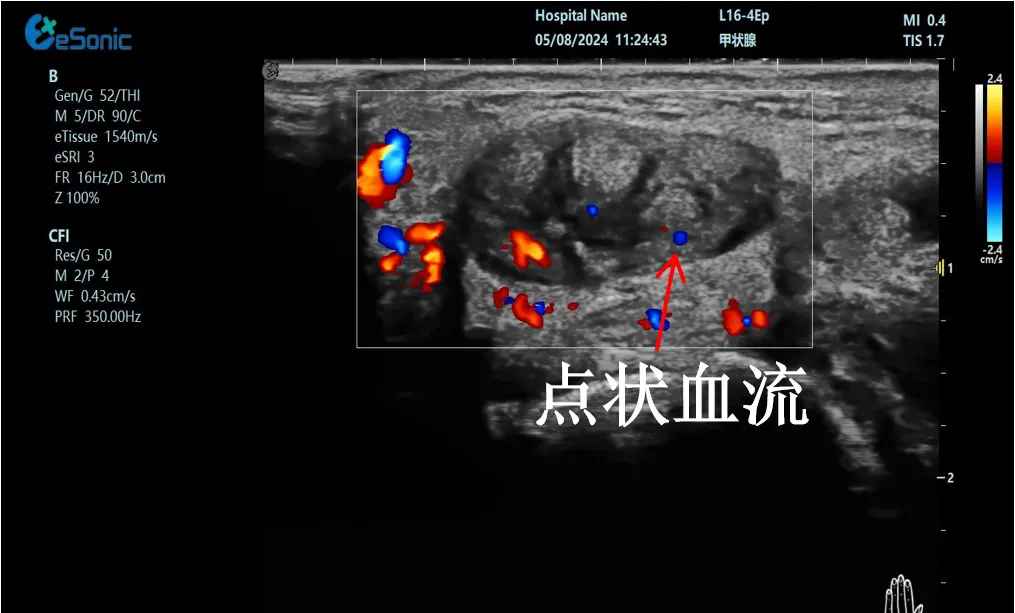

mFlow?技术在腱鞘炎诊疗中的应用

【背景】:左手腕关节第四腔室腱鞘炎。

【痛点】:普通彩色多普勒不敏感,只能看到细小点状血流,容易被忽略,难以进行分级诊断和疗效评估。

【方案】:新航娱乐医疗(ESI)超微血流技术可以看到腔室内肌腱周围环状血流,可充分提示:

1、处于炎症活动期;

2、根据血流进行分级诊断提示1级;

3、治疗后根据血流多少评估疗效(见右下图:治疗10天后复查超声,微血流图像血供消失)。